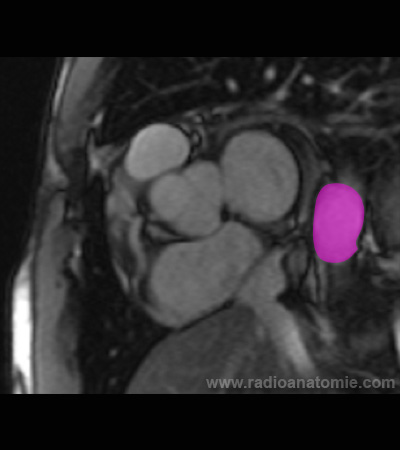

Radioanatomie et plans de coupe en IRM cardiaque

Aorte descendante